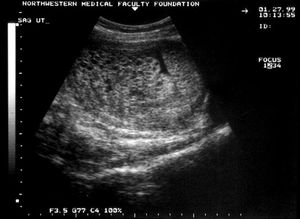

Ultrasounds - Hydatidiform moleByJohn R. Lurain, MDAugust 21st 2019Ultrasonography plays a critical role in the diagnosis of both complete and partial molar pregnancy.

Hydatidiform mole: Recognition and managementByJohn R. Lurain, MDMarch 13th 2019Molar pregnancies may be associated with serious morbidity so prompt diagnosis, appropriate management, and follow-up are essential.